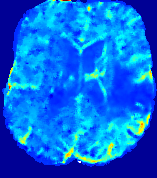

LesionRefer to captionRefer to captionRefer to captionRefer to captionRefer to captionRefer to caption𝐕rgbsubscript𝐕𝑟𝑔𝑏{\bf{V}}_{rgb}Refer to captionRefer to captionRefer to captionRefer to captionRefer to captionRefer to caption𝐕2subscriptnorm𝐕2{\|\bf{V}}\|_{2}Refer to captionRefer to captionRefer to captionRefer to captionRefer to captionRefer to captionRefer to caption3.53.53.52.82.82.82.12.12.11.41.41.40.70.70.70.00.00.0(mm/s)𝑚𝑚𝑠(mm/s)D𝐷DRefer to captionRefer to captionRefer to captionRefer to captionRefer to captionRefer to captionRefer to caption0.0200.0200.0200.0160.0160.0160.0120.0120.0120.0080.0080.0080.0040.0040.0040.0000.0000.000(mm2/s)𝑚superscript𝑚2𝑠(mm^{2}/s)Slice #1Slice #2Slice #3Slice #4Slice #5Slice #6

Figure 4: PIANO feature maps for another patient in the ISLES 2017 training set, where the lesion is located in the right hemisphere. Top row: segmented stroke lesion region (white) on different slices. The corresponding slices for the PIANO feature maps are shown in the following rows.

For a better insight into an estimated velocity field 𝐕𝐕{\bf{V}} and diffusion field 𝐃𝐃{\bf{D}}, we compute the following maps: (1) 𝐕rgbsubscript𝐕𝑟𝑔𝑏{\bf{V}}_{rgb}: Color-coded orientation map of 𝐕=(Vx,Vy,Vz)T𝐕superscriptsuperscript𝑉𝑥superscript𝑉𝑦superscript𝑉𝑧𝑇{\bf{V}}=(V^{x},V^{y},V^{z})^{T}, obtained by normalizing 𝐕𝐕{\bf{V}} to unit length and mapping its 3 components to red, green, blue respectively; (2) 𝐕2subscriptnorm𝐕2\|{\bf{V}}\|_{2}: 222 norm of 𝐕𝐕{\bf{V}}; (3) D𝐷D: scalar field in Eq. 5.

Fig. 3 and Fig. 4 show the PIANO feature maps estimated from two ISLES 2017 patients: all are highly consistent with the lesion in both cases. Details of the blood flow trajectories are revealed in 𝐕rgbsubscript𝐕𝑟𝑔𝑏{\bf{V}}_{rgb} by the ridged patterns and the sharp changes of colors in the unaffected (right) hemisphere, while the flat patterns appearing within the lesion provide little directional information about the velocity and indicate low velocity magnitudes. Velocity magnitudes are more directly visualized via 𝐕2subscriptnorm𝐕2\|{\bf{V}}\|_{2}, from which one can easily locate the lesion where 𝐕2subscriptnorm𝐕2\|{\bf{V}}\|_{2} is low. D𝐷D also indicates lower diffusion values in the lesion, though with less contrast potentially due to the fact that it captures the accumulated effect of CA diffusion at the voxel-level.